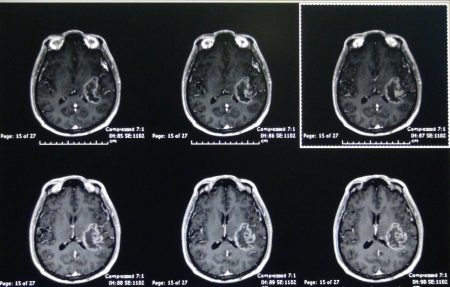

รศ.นพ.กฤษณพันธ์ บุณยะรัตเวช ศัลยแพทย์เฉพาะทางด้านประสาทศัลยศาสตร์ โรงพยาบาลจุฬาลงกรณ์ สภากาชาดไทย อธิบายถึงความแตกต่างของการผ่าตัดสมองแบบผู้ป่วยตื่น(Awake Craniotomy) และการผ่าตัดสมองโดยทั่วไปว่า การผ่าตัดสมองโดยทั่วไปผู้ป่วยจะไม่รู้สึกตัวจนกระทั่งการผ่าตัดเสร็จสิ้นทุกกระบวนการ แต่การผ่าตัดสมองแบบผู้ป่วยตื่นนั้น ผู้ป่วยจะถูกปลุกให้ตื่นขึ้นมาในช่วงหนึ่งของการผ่าตัดเพื่อให้แพทย์สามารถตรวจสอบการตอบสนองของผู้ป่วย เช่น การพูด การขยับแขนหรือขา การเปิด-ปิดตา และการรับรู้ความรู้สึก ฯลฯ เพื่อให้แน่ใจว่าการผ่าตัดสมองนั้นไม่ได้กระทบสมองส่วนอื่นๆที่สำคัญของผู้ป่วย การผ่าตัดรูปแบบนี้เป็นเทคนิคการผ่าตัดที่ใช้สำหรับผ่าตัดเนื้องอกในสมองหรือการผ่าตัดฝังเครื่องกระตุ้นสมอง ซึ่งบริเวณสมองส่วนที่ผ่าตัดนั้นจะอยู่ใกลกับสมองส่วนทีมี่ความสำคัญ เช่น เป็นสมองส่วนควบคุมการพูด การเคลื่อนไหวแขน ขา การกลอกตา การรับรู้ความรู้สึก เป็นต้น

รศ.นพ.กฤษณพันธ์ กล่าวสรุปถึงประโยชน์ของการผ่าตัดสมองแบบผู้ป่วยตื่น (Awake Craniotomy) ว่า เป็นการผ่าตัดที่มีประโยชน์อย่างยิ่งเนื่องจากการผ่าตัดด้วยวิธีนี้ช่วยให้ศัลยแพทย์สามารถผ่าตัดรักษาในกลุ่มโรคที่มีอาการอยู่ใกล้กับสมองส่วนที่มีความสำคัญได้เป็นอย่างดี อีกทั้งยังเป็นการรักษาที่มีประสิทธิภาพมาก เพราะในระหว่างการผ่าตัด แพทย์สามารถให้การรักษาผู้ป่วยได้อย่างเต็มที่ที่สุดและเห็นการตอบสนองของผู้ป่วยได้อย่างชัดเจน นอกจากนี้การผ่าตัดสมองแบบผู้ป่วยตื่นจะสำเร็จลุล่วงไม่ได้เลย หากขาดการประสานงานที่ลงตัวระหว่างศัลยแพทย์และวิสัญญีแพทย์ ที่ต้องทำให้ผู้ป่วยหลับและตื่นขึ้นมาเพื่อทำการทดสอบการตอบสนองต่างๆ ให้เป็นไปอย่างราบรื่นที่สุด ที่ผ่านมาโรงพยาบาลจุฬาลงกรณ์สามารถให้การผ่าตัดรักษาผู้ป่วยด้วยวิธีการนี้สำเร็จไปแล้วกว่า 80 ราย ซึ่งในอนาคตทีมแพทย์โรงพยาบาลจุฬาลงกรณ์จะพัฒนาการผ่าตัดสมองแบบผู้ป่วยตื่นให้มีประสิทธิภาพมากยิ่งขึ้นเพื่อช่วยให้ผู้ป่วยกลับมามีคุณภาพชีวิตที่ดีขึ้นได้ต่อไป